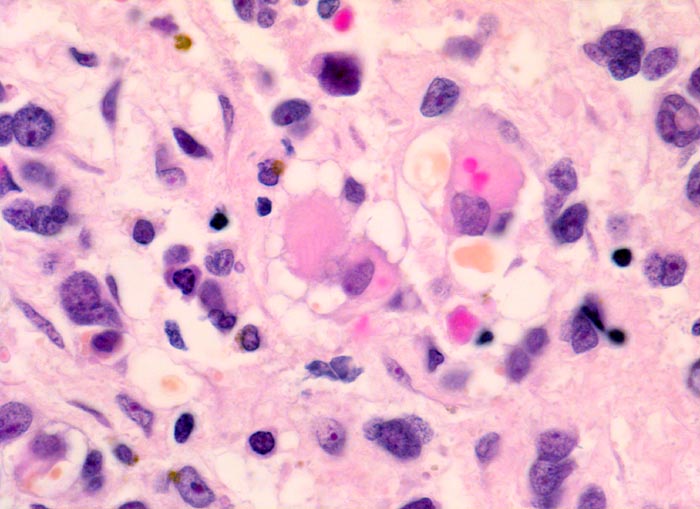

embryonales Rhabdomyosarkom

Neben primitiven ovalen und spindeligen Zellen mit sehr wenig Zytoplasma sind in der Bildmitte Rhabdomyoblasten mit vakuolisiertem Zytoplasma erkennbar. Dabei handelt es sich um sogenannte Spinnwebenzellen. Die Vakuolen entstehen durch herausgelöstes Glykogen.

Schmerzloser rasch wachsender Tumor im oberen inneren Quadranten der Orbita mit Verdrängung des Bulbus nach temporal. Diplopie.

Histologie

Vergrösserung

630

Alter